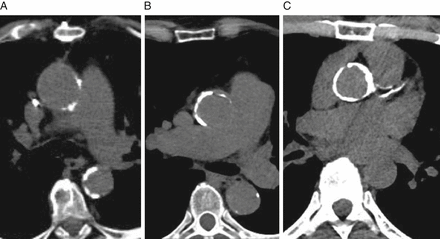

TAVI Work - Up

Transthoracic Echo

Transesophageal Echo

- Annulus dimensions

CT Coronary

- Aortic annulus dimensions

- Aorto-Iliac peripheral arterial disease

-Distance between coronary ostia and aortic annulus

Angiogram